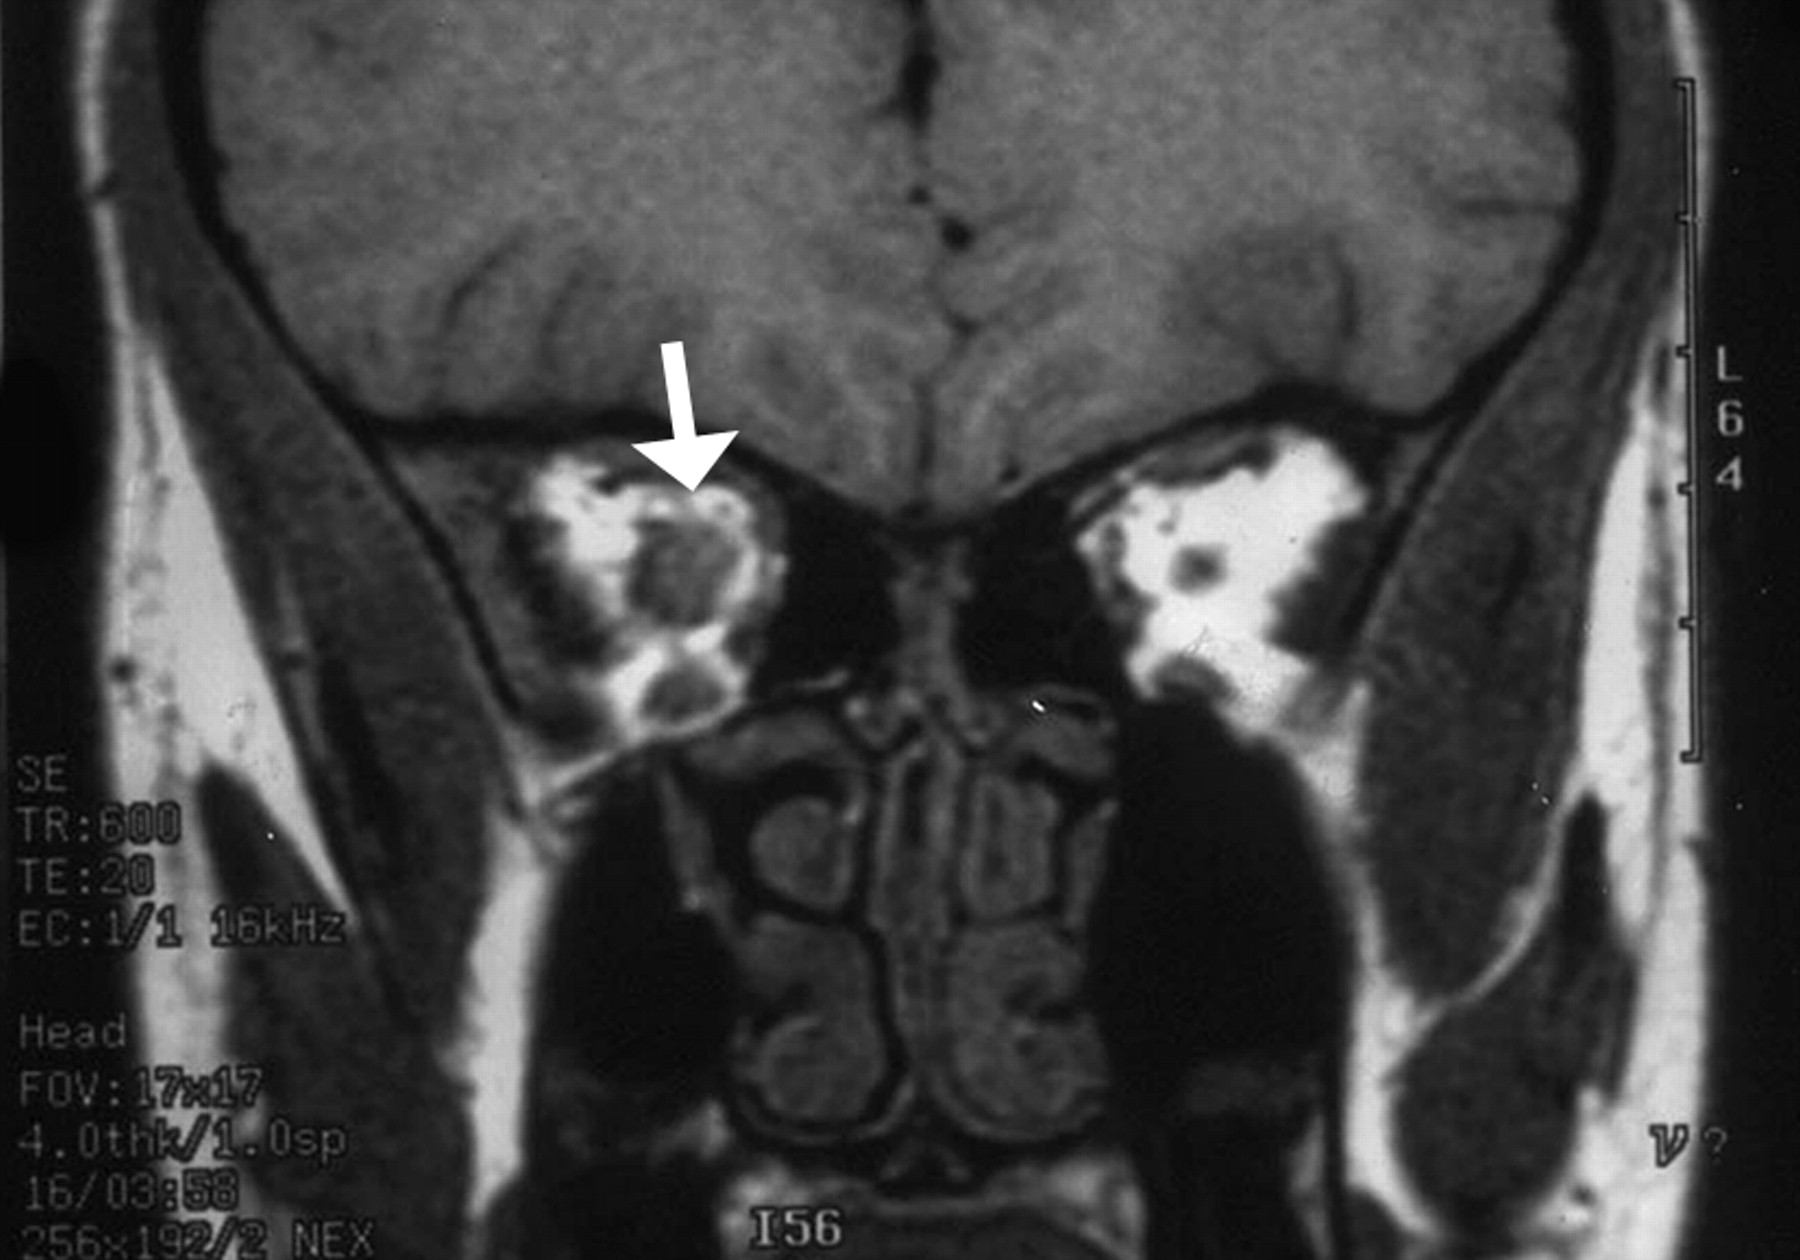

mass.jpg